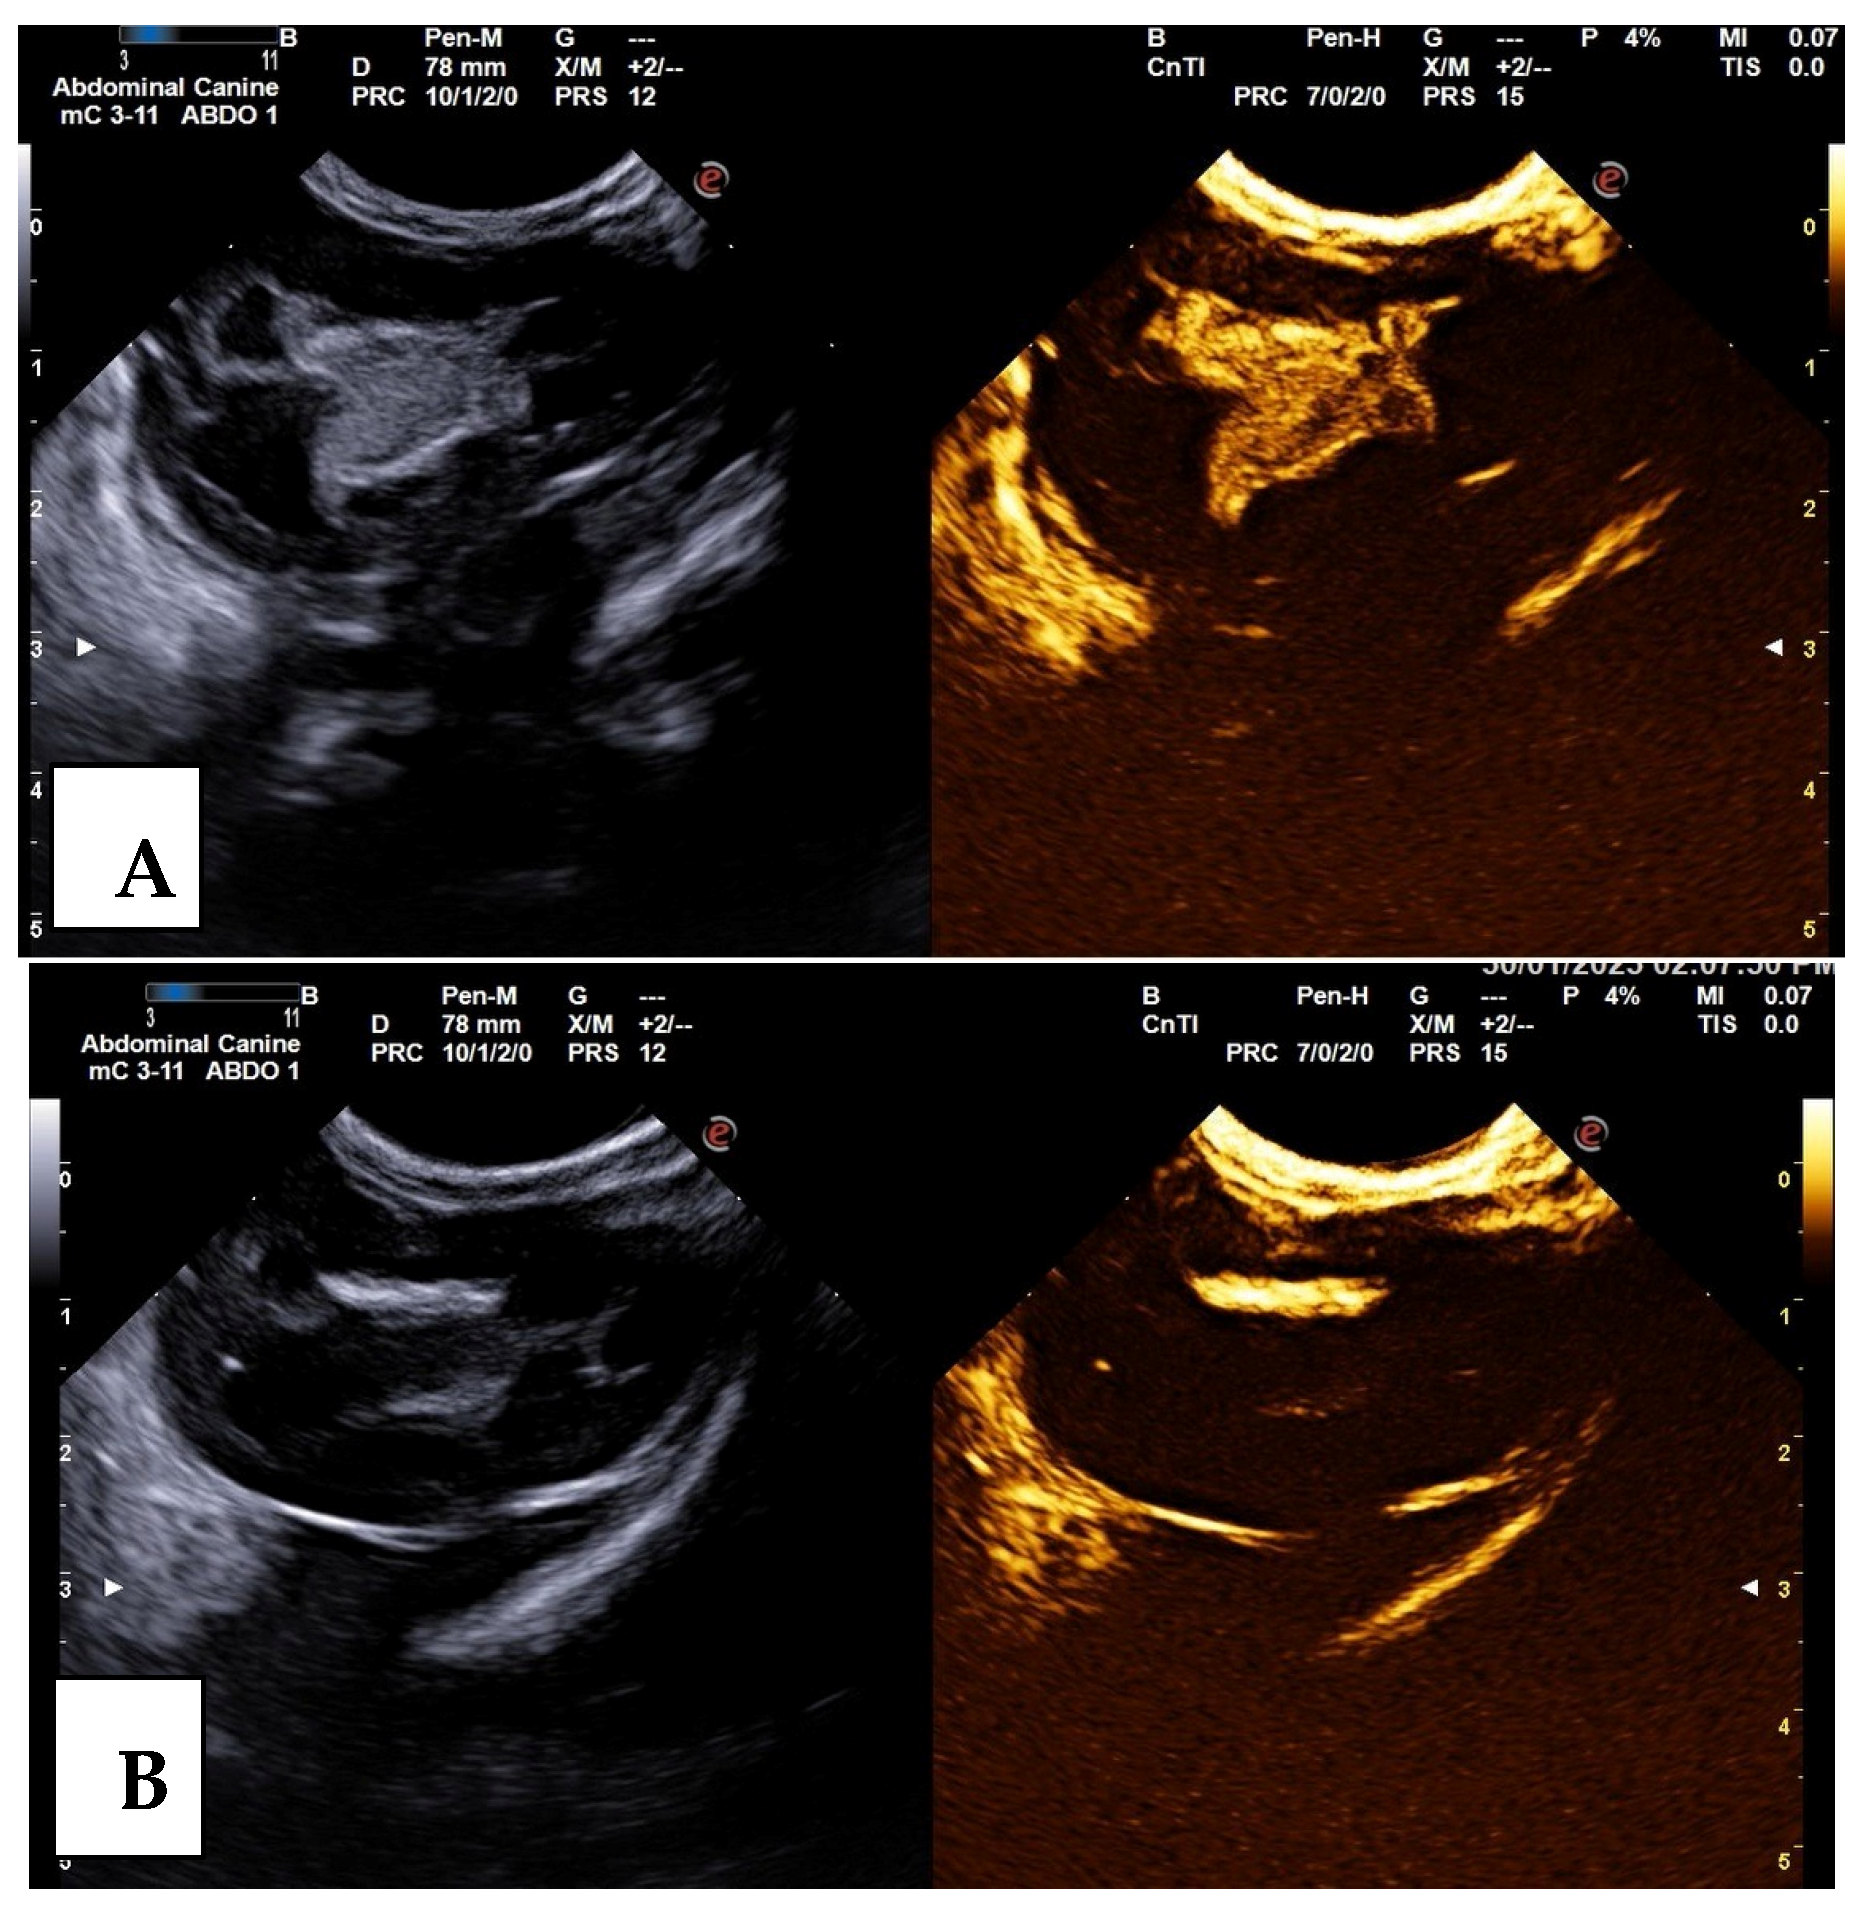

Figure 2.

Vesicoureteral reflux (VUR) grade II in the left kidney demonstrated on the contrast-enhanced voiding urosonography (CE-VUS) in the dog presented in Figure 1. On CE-VUS microbubbles are visible in the renal pelvis (A), enabling the diagnosis of VUR. (B) The renal pelvis in the corresponding image before the contrast agent administration.